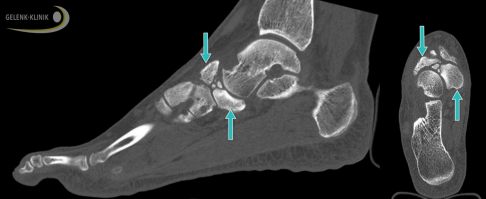

Die Schnittbilder der digitalen Volumentomografie (DVT) zeigen ein gebrochenes Kahnbein bei Müller-Weiss-Syndrom. Die Fraktur des Kahnbeins ist in der Seitenansicht des Fußes (links) und der Ansicht von oben (rechts) durch Pfeile gekennzeichnet. © Gelenk-Klinik

Die Digitale Volumentomographie (DVT) zeigt den Defekt und die Fehlstellung des Kahnbeins bei Müller-Weiss-Syndrom im Stehen (Pfeile). Diese Aufnahmen unter Belastung nutzt der Spezialist für die Therapieplanung, die er an die Situation des Patienten anpasst. © Gelenk-Klinik